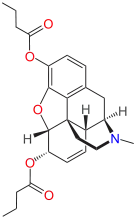

3,6-diesters of morphine

- Acetylpropionylmorphine

- 3,6-Dibutanoylmorphine

- Diacetyldihydromorphine (dihydroheroin, acetylmorphinol)

- Dibutyrylmorphine

- Dibenzoylmorphine (first designer drug)

- Diformylmorphine

- Dipropanoylmorphine

- Heroin (diacetylmorphine)

- Nicomorphine

Structures

| 3,6-diesters of morphine | ||||

|---|---|---|---|---|

Acetylpropionylmorphine Acetylpropionylmorphine |

3,6-Dibutanoylmorphine |  Diacetyldihydromorphine Diacetyldihydromorphine(dihydroheroin, acetylmorphinol) | ||

Dibutyrylmorphine Dibutyrylmorphine |

Dibenzoylmorphine Dibenzoylmorphine |

Diformylmorphine Diformylmorphine | ||

Dipropanoylmorphine Dipropanoylmorphine |

Heroin Heroin(diacetylmorphine) |

Nicomorphine Nicomorphine | ||